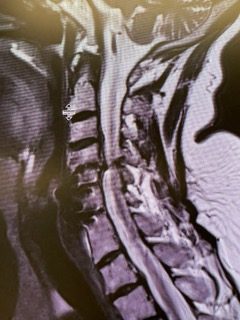

Back:

Revision Surgery Treats Intractable Neck Pain & Cervical Deformity

Author: Benjamin R. Cohen M.D., F.A.A.N.S., F.A.C.S., Read More!